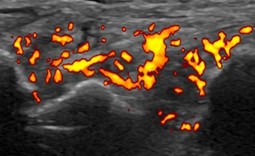

X線検査では、RAが進行すると関節周囲の骨粗鬆症に加えて、関節裂隙の狭小化、骨びらん、強直などがみられます。しかし、RA発症の初期(図1、図3)ではこうしたX線の変化はほとんどみられません。関節エコー検査(図2)やMRI検査(図4)を用いるとX線検査では認めることのできないRAの早期の変化である活動性滑膜炎や骨びらんを確認することができるので、RAの早期診断と早期治療につながります。

3. 関節エコー外来

当院では、毎月1回(土曜日)にリウマチ専門医による関節エコー外来を実施しています。

関節エコーは、関節リウマチの早期診断や治療効果の評価に有用な検査です。